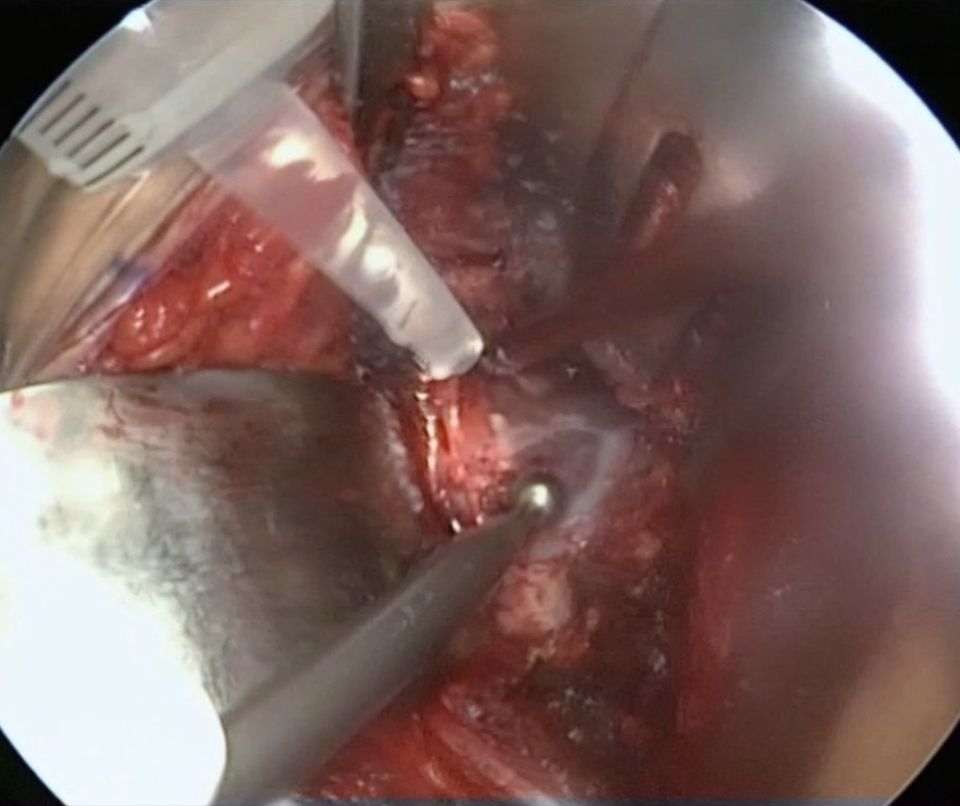

If this targeted ROM is not achieved, and the acetabular reorientation is correct an additional head-neck offset correction has to be performed. This offset correction is done via a classical direct anterior approach (Smith-Peterson interval) utilizing the interval medial of the tensor and lateral of the rectus and the sartorius muscle. The intervall between the M. sartorious and the M. tensor fascia latae (TFL) is bluntly dissected and two blunt curved Hohmann retractors are inserted to expose the capsule of the hip joint. The proximal insertion of the M. rectus femoris is bluntly liberated with a gauze-covered Cobb-raspatorium. Placement of a broad Hohmann retractor on the anterior acetabular column under the proximal insertion of the M. rectus femoris. T-shaped capsulotomy. The medial aspect of the capsulotomy should occur under visualization to avoid accidental damage to the labrum. Intracapsular placement of both blunt Hohmann retractors above and below the femoral neck (Fig 17).

Now remodulation of the femoral asphericity with a high-speed burr can be performed. The remodulation should extend right up to the acetabular labrum, without touching or damaging the labrum. Mobilization of the leg to visualize the hip joint and control the impingement-free range of motion. The minimum acceptable range of motion is 120° of flexion and 30° of internal rotation under simultaneous 90° of flexion. Radiographic control: A complete removal of the femoral asphericity is achieved (Fig 18).